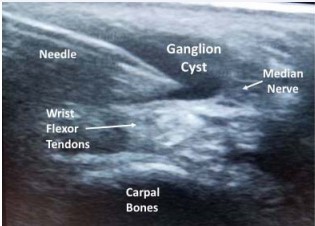

Point-of-care ultrasound examination revealed a 2.0 x 0.8 x 1.8 cm fluid filled cyst within the left carpal tunnel that appeared to be contacting the median nerve (Figures 1,2). Further evaluation with MRI confirmed the cyst amidst the flexor tendons within the carpal tunnel. The median nerve was being directly contact by the cyst and the nerve was located to the ulnar aspect of the cyst. Characteristics of the cyst were consistent with a ganglion cyst. Subsequently, the patient underwent an ultrasound guided needle aspiration of 7cc of thick serous fluid and corticosteroid injection of the ganglion cyst (Figure 3). The wrist was wrapped with an elastic compressive dressing and the patient was counseled on activity modification. She followed up in clinic at two months and again at six months from the ultrasound guided procedure. At both visits, the patient had significant reduction

Figure 2: Long axis ultrasound image of ganglion cyst within the carpal tunnel.

Figure 3: Ultrasound guided needle aspiration of ganglion cyst within the carpal tunnel.